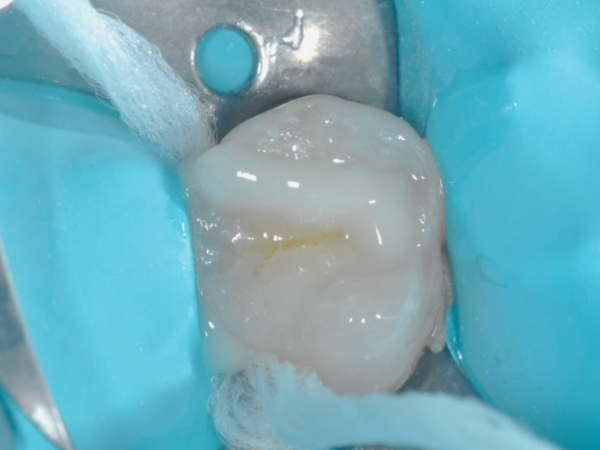

– 자연스러운 회복 반응

![마곡역치과_4. 인레이 치료 후 통증 생기는 이유 [ 자연스러운 회복? 문제 신호?] 관련 이미지 1](https://pub-9f2bb3498faf4d1d8714b41df24753e3.r2.dev/content/clinics/archive/rlg13v0fli/naver_blog/dia_dental/assets/by_hash/fb3792c9c9ca53f2fc268f9d9b2c91caa5b0368d4162302f78fb2036d0c4194e.png)

마곡역치과_치아 삭제

가장 흔한 경우입니다.

충치 제거 과정에서 치수(신경조직) 가까이까지 삭제가 이루어졌거나

치아가 기존에 이미 미세한 자극을 반복적으로 받아왔던 경우,

치료 후 일시적으로 신경이 민감해질 수 있습니다.

찬 음식에 시리거나 씹을 때 순간적인 시큰거리고

가만히 있을 땐 통증 없는 특징이 있습니다.

이런 경우엔 대부분 1~2주 안에 점차 호전됩니다.

딱딱하거나 차가운 음식은 잠시 피하시고,

과도한 이갈이나 이 악물기도 조심해주세요.

진통제가 필요할 정도의 통증이 아니라면

자연스러운 회복 반응으로 보고 경과를 지켜보면 됩니다.